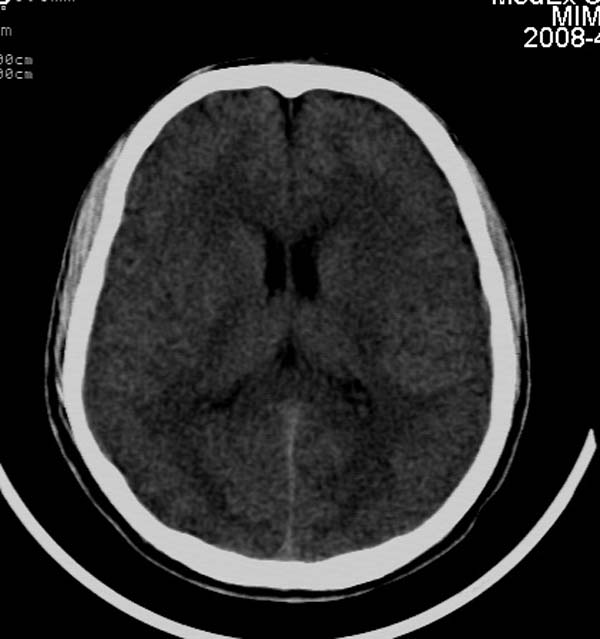

患者,男,24岁。头面部外伤后意识障碍1小时。

考虑右侧天幕缘少量蛛网膜下腔出血;建议:必要时复查。

1)考虑少量蛛网膜下腔出血;建议:必要时复查。2)桥前池及左侧环池表皮样囊肿可能。建议:行mri检查。

1)考虑蛛网膜下腔出血;建议:复查。2)桥前池及左侧环池表皮样囊肿可能。建议:行mri检查。

考虑右侧天幕缘区域少量蛛网膜下腔出血。

一侧密度增高,是否考虑为硬膜下血肿,前额血肿真好对冲伤,桥小脑脚增宽建议进一步检查